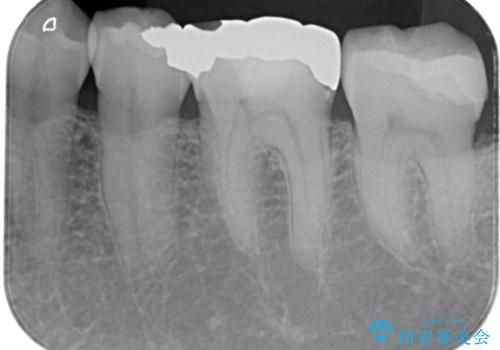

- 銀歯2本の下が虫歯になっていたので、フルジルコニアクラウンとセラミックインレーで治療を行いました。

適合が良い被せ物を入れるために、歯の境としっかり合わせた仮歯を入れ、歯茎の状態を良くしてからシリコンで型取りをしています。